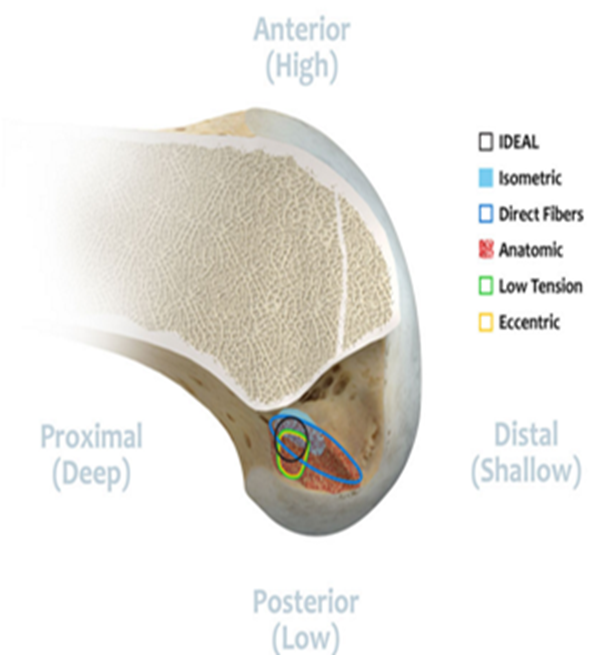

交叉韧带重建理念与技术的变迁:等长-解剖-类等长-功能束重建-“I.D.E.A.L”。三位外科医生在ACL重建领域加起来拥有70年的临床和研究经验。作为一个团队,他们对大量ACL重建解剖学,组织学,生物力学和临床数据进行了全面研究,并推荐使用首字母缩略词“I.D.E.A.L”作为描述完成股骨隧道指南的缩写术语。

I.D.E.A.L. femoral tunnel location (黑色圆圈位置为理想股骨骨道位置)。